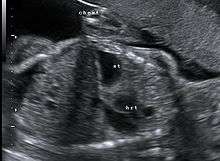

Survival rates for infants with this condition vary, but have generally been increasing through advances in neonatal medicine. Work has been done to correlate survival rates to ultrasound measurements of the lung volume as compared to the baby's head circumference. This figure known as the lung to head ratio (LHR).